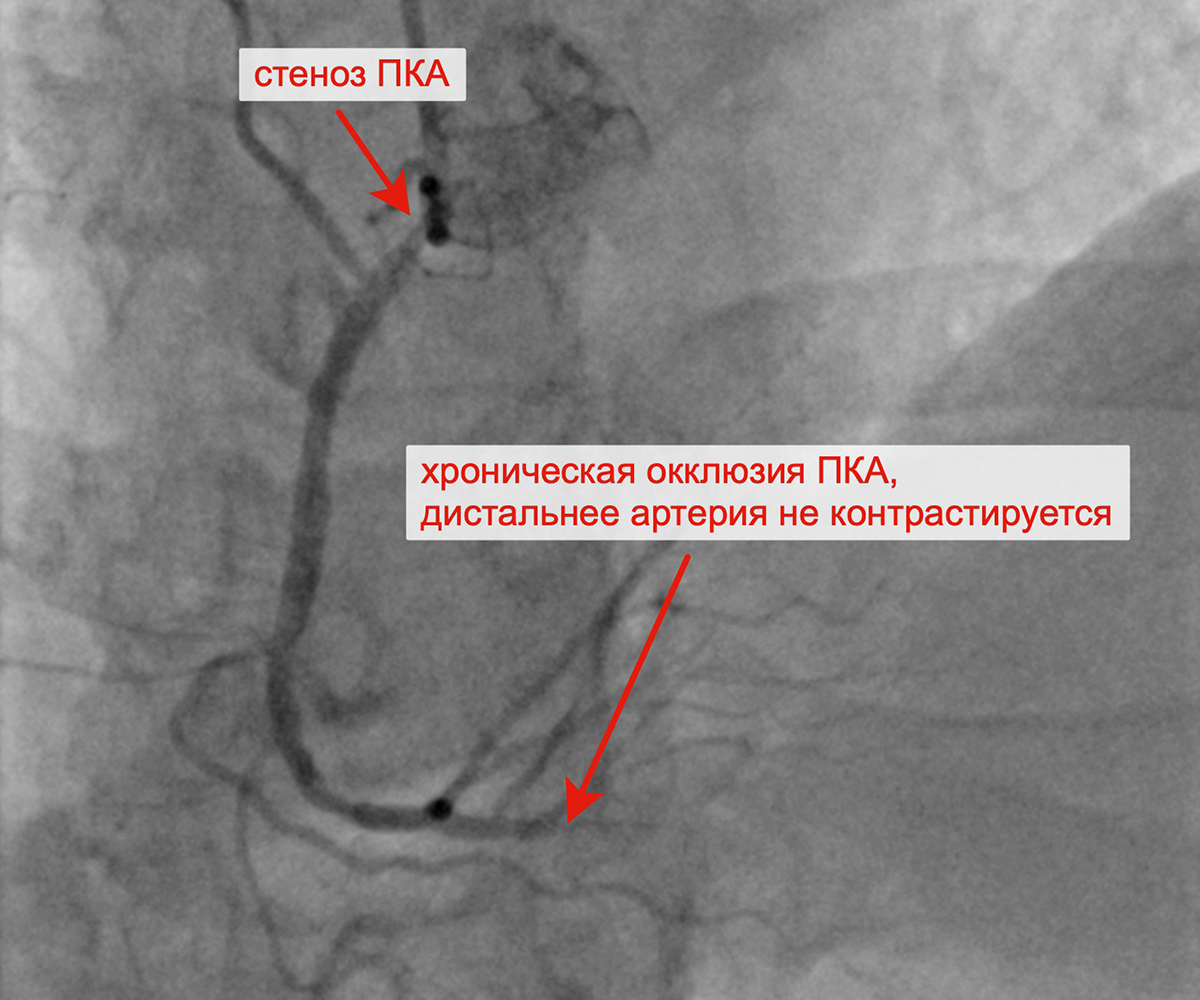

ПРАВАЯ КОРОНАРНАЯ АРТЕРИЯ (ПКА): изменения в виде неровности контуров, атерокальциноза ЛКА, стеноз устья и проксимального сегмента ПКА 70%, хроническая окклюзия проксимального сегмента ЗМЖА.

Хроническая окклюзия правой коронарной артерии Реканализация ПКА с контрастированием дистального русла